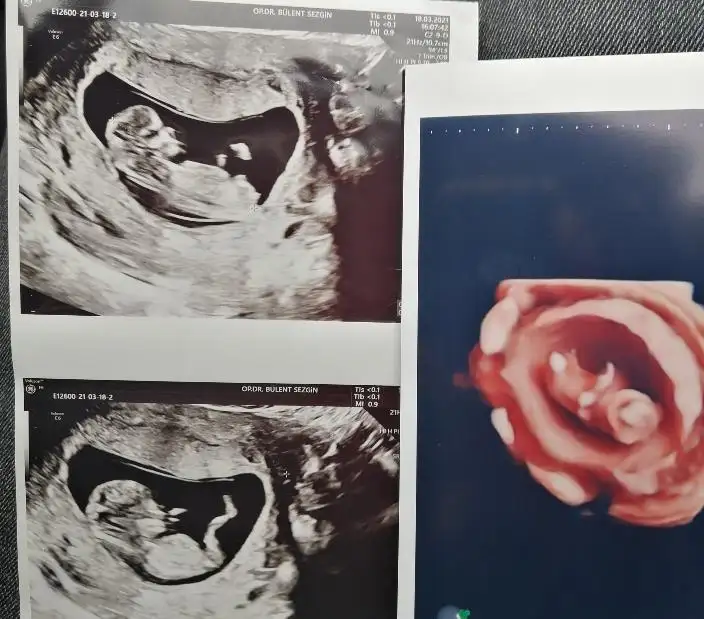

Merhaba 11+4de size usg atmıştım kız gibi demistiniz şimdi 14+5 atıyorum tekrar yorumlarmısiniz hala söylemedi doktorErkek görünüyor

Ay ben ikra kadar anlamam ama kız gibi geldi yaMerhaba 11+4de size usg atmıştım kız gibi demistiniz şimdi 14+5 atıyorum tekrar yorumlarmısiniz hala söylemedi doktor

11+4 de kız demiştim ama 14+5 de artık organı oluşmuş oluyor bakalım hayırlısı olsun tipi kız gibiMerhaba 11+4de size usg atmıştım kız gibi demistiniz şimdi 14+5 atıyorum tekrar yorumlarmısiniz hala söylemedi doktor

Teşekkür ederim doktorda ben kız diyorum ama emin değilim dedi netlesince yazicam size11+4 de kız demiştim ama 14+5 de artık organı oluşmuş oluyor bakalım hayırlısı olsun tipi kız gibi